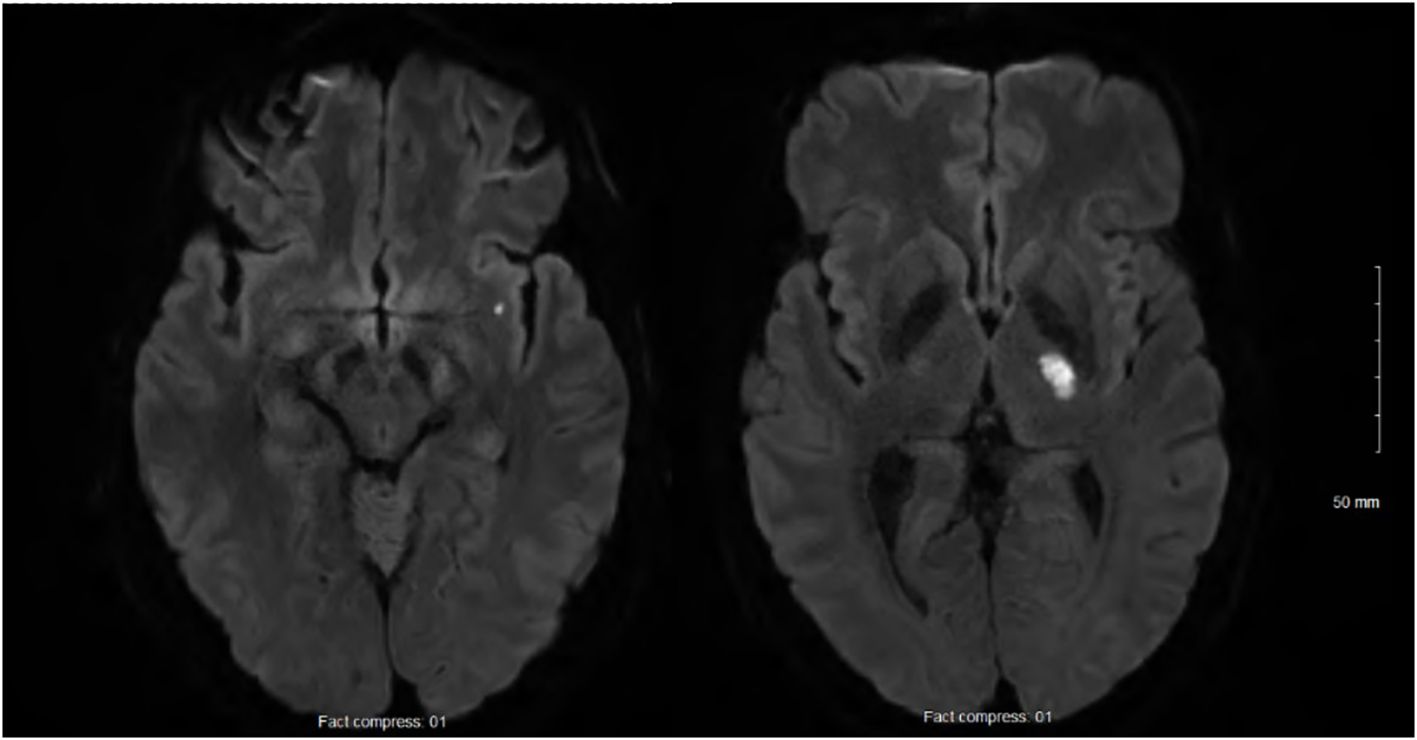

At 24h after walking outside on a cold winter day, he developed pain in both legs and finger cyanosis on his right hand, which he attributed to frostbite despite wearing appropriate clothing. He had never experienced Raynaud’s phenomenon. At 2 weeks later, as he was improving, he woke up with recurrent leg pain and right-sided weakness. The physical exam showed normal vital signs and temperature, right hemiparesis, hypoesthesia limited to the medial aspect of the dorsum of the right foot and the first two toes, and normal myotatic reflexes. The last three fingers of the right hand were lightly cyanotic, combined with a subungual hematoma on the 5th. There was a slight orthostatic bluish discoloration of the lower limbs, worse on the right. There was no livedo racemosa and no dermatological manifestations. Brain magnetic resonance imaging (MRI) confirmed two acute small-sized infarcts consistent with small artery occlusion, without chronic ischemic or hemorrhagic changes (Figure 1). Antiplatelet therapy was initiated, consisting of aspirin (combined with clopidogrel for 3 weeks). Over the following days, he developed a thoraco-abdominal macular rash, which was initially thought to possibly result from allergy. However, the skin prick tests and drug challenges including aspirin and clopidogrel were negative, and the rash resolved spontaneously while the antiplatelet agents were continued.

Figure 1. Acute small-sized infarcts of the left internal capsule and sub-insula, and no chronic infarcts, leucoaraiosis, or microbleeds.

The investigation found no common cause of IS. Lacunar IS due to arteriolosclerosis is unlikely in the absence of chronic ischemic or hemorrhagic changes on brain MRI. The investigation documented inflammation, but positron emission tomography and skin biopsy showed no evidence of vasculitis. Moreover, the patient’s favorable outcome in the absence of immunosuppressant treatment does not support vasculitis. We believe that our patient had an IS due to MKD-related inflammation and small artery occlusion. Abnormal activation of sophisticated interlinks between innate immunity and hemostasis is involved in thromboembolic complications of autoinflammatory diseases (19). We hypothesize that our patient’s risk factors for arteriosclerosis, including cigarette and cannabis smoking and dyslipidemia, and actual atherosclerotic plaques contributed to the systemic prothrombotic environment of thromboinflammation. Unfortunately, the biomarkers of endothelial dysfunction (e.g., vascular cell adhesion molecule-1, intercellular adhesion molecule 1) were not measured. The presence of cryofibrinogen and monoclonal gammopathy raises doubt about the IS etiology, and there is a potential for overlapping of different causes. Whereas essential cryofibrinogenemia is frequently asymptomatic, symptomatic patients typically present in the fifth decade with cold intolerance, skin ulcers affecting exposed surfaces, livedo, and thrombosis (20, 21).However, in the patient that we report here, there were no dermatological manifestations or livedo, and the blood tests did not find cryofibrinogen at IS presentation and on a subsequent measurement (Figure 2). Cryofibrinogen was variably detected from 3 months post-stroke until canakinumab treatment. Skin biopsy revealed nonspecific changes, without plugging of deep and superficial blood vessels by cryofibrinogen-containing thrombi (20, 21). Cryofibrinogenemia in this patient likely resulted from autoinflammation rather than being the cause of IS and skin ulcers (22). While skin biopsy findings could be consistent with PG, occurring in association with the documented monoclonal gammopathy of unknown significance, it can also represent a manifestation of MKD or its treatment with anti-IL1 agents. Histopathology of skin biopsies in MKD is varied and under-reported to date (23). This patient had monoclonal gammopathy but no evidence of multiple myeloma. Monoclonal gammopathy may increase the risk of thrombosis. However, monoclonal gammopathy of thrombotic significance is generally not associated with inflammation, and the absence of recurrent thromboembolic events when no treatment targeting this condition has been initiated does not support this diagnosis (24).